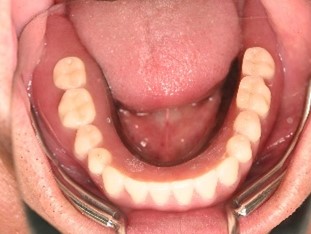

After

【義歯を装着したところ】

【義歯を外したところ】